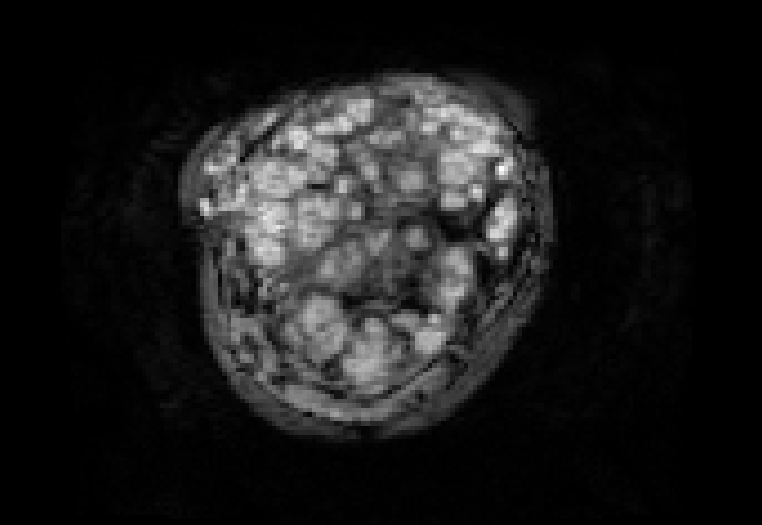

This atlas and the linked publication [1] aim to give a visual overview over T2-weighted anatomical imaging and T2* relaxometry placental data. Both have been widely used in the last years to assess placental structure and function in-vivo [2-10].

Data from healthy controls is displayed over GA, different acquisition choices and possible dynamic effects are depicted and placentae from different cohorts affected by complications are shown.

Display description: All placentae are shown in maternal coronal plane (See A). The slice with the largest placental volume was chosen. The same colormap was chosen for all placentae (See B).